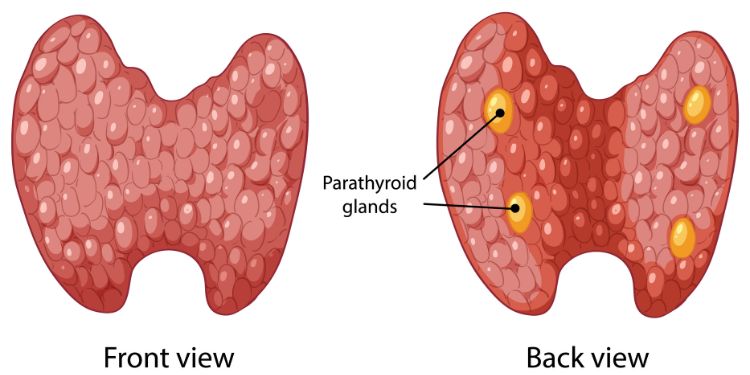

Thyroid Cancer

ISSN :2574-4496

Thyroid Cancer: Stay informed on the latest Metformin, Glutathione and Selenium research findings to manage and treat this chronic condition.